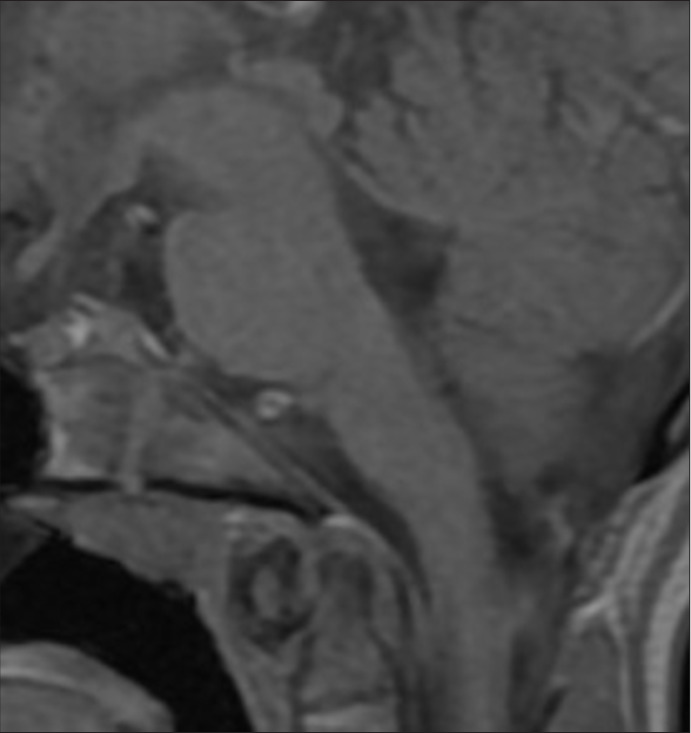

Case description: A 12-year-old girl presented with progressive gait disturbances, disequilibrium, diplopia due to right-sided abducens paresis, left-sided facial paresis (HB grade II), headaches, nausea, and vomiting over the past 6 months. Magnetic resonance imaging (MRI) revealed an intrinsic lesion of the brainstem not present on MRI 4 years prior. A microsurgical gross total resection, including resection of cyst wall, was performed. The pathology report diagnosed the lesion as an epidermoid cyst. The patient improved significantly after resection.